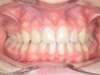

ADULTE

Cas 1 : Description

Après